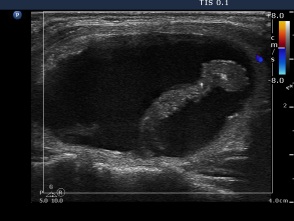

Second session of sclerotherapy (third row of images):

The second session was performed nine days after the previous one. The nodule became a bit larger. Now we could aspirated 15 mL brown fluid form the nodule, therafter we injected 5 mL ethanol.